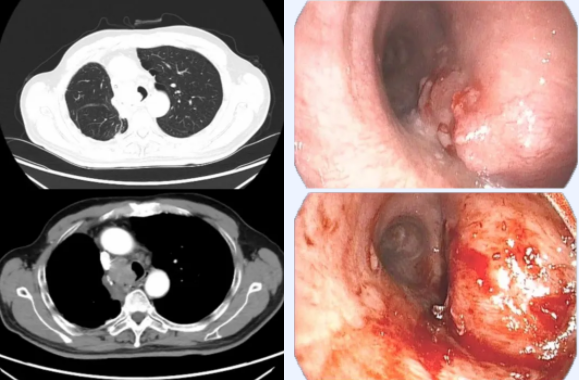

该患者因肺部恶性肿瘤入院治疗,CT显示其气管下段右侧壁有一巨大肿物,部分堵塞气管及右侧主支气管开口。气管镜下可见气管下段与右侧支气管处境极为险峻——不仅受到外部肿瘤压迫导致严重狭窄,还有新生肿瘤突破管壁侵入内部。更为棘手的是,这个位于气管腔内的肿瘤血供异常丰富,轻微触碰就会导致出血,而出血形成的血凝块会进一步堵塞本已狭窄的气管,甚至导致窒息,这使得任何操作都面临极高风险。